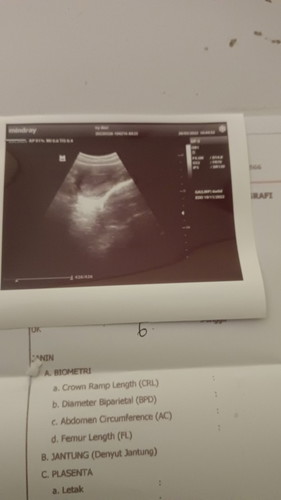

Di umur debay 5 minggu blm keliatan kantong dan janin nya. Sedih

Hari ini di klinik tiga mandiri

positif thinking aja bund. dl sy jg gt blm keliatan sempat sedih cerita kesuami trus suami blg percaya aja kalau beneran hamil, yakin aja. alhamdulillah pas di 7w udh nampak kantong+janin bund. pdhl pas 5w sy usgnya transvaginal bund tp blm nampak msh penebalan dinding rahim bund dan dokternya gak berani blg hamil, mau haid jg sama penebalan dinding rahim jg katanya. makanya pulang2 sy nangis bund hehe